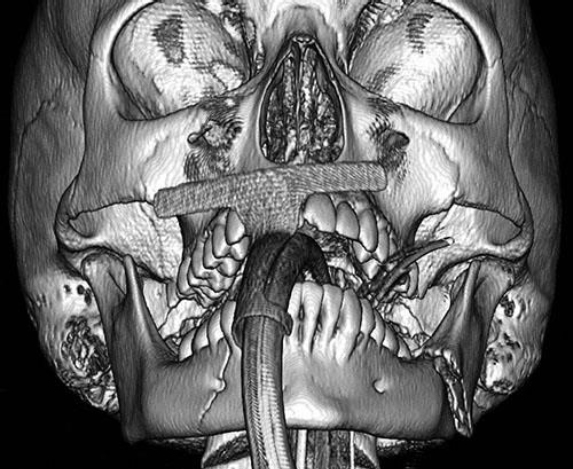

A 25-year-old Caucasian man presents with a self-inflicted gunshot wound to the face resulting in significant soft-tissue and bony injuries. Following initial stabilization and debridement, there is a 12-cm mandibular defect extending from the right angle to the left parasymphysis. Which of the following is the most appropriate bony reconstruction for this defect? A) Fibula osteocutaneous flap B) Iliac crest bone graft C) Medial femoral condyle osteocutaneous flap D) Parascapular osteocutaneous flap E) Radial forearm osteocutaneous flap

The correct response is Option A. The fibula flap provides the greatest bony length for reconstruction which is necessary for this large defect. While leaving the proximal and distal 5-6 cm is critical to preservation of donor site function, often a 20+ cm flap can be harvested. The fibula is also able to tolerate multiple osteotomies to reconstruct the mandibular contour as well as adequate bone stock for subsequent dental implant rehabilitation. The parascapular, radial forearm, and medial femoral condyle flaps do not provide adequate bony length for this defect. The parascapular flap is a versatile flap which can be harvested with large volume for soft tissue reconstruction as well as bone from the scapular tip. However, this bone is relatively small and thin, therefore not easily amenable to dental implants. Chimeric flaps containing skin, muscle, and bone can be also harvested on the pedicle for extensive defects. Unfortunately, the flap is typically harvested either in a lateral decubitus or prone position, which often requires patient repositioning during the reconstruction. The radial forearm flap is another common flap used in head and neck reconstruction, but the amount of bone that can be harvested is limited due to concerns for donor site morbidity (fracture of the residual radius). The radial forearm osteocutaneous flap is rarely used. The medial femoral condyle flap is a popular source for vascularized bone defects, but it also only provides a small block of corticocancellous bone and therefore is more popular in hand surgery or smaller defects. An iliac crest bone graft is nonvascularized and more commonly reserved for smaller defects (less than 4 to 5 cm). Large nonvascularized bone is likely to result in bony absorption and non-union. The fibula flap provides the greatest bony length for reconstruction, which is necessary for this large defect. 2023